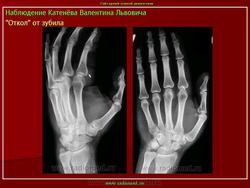

Инородное тело - зуб в пищеводе.

Приложения:

inorodnoe_telo_obstrukcii._-zub_v_pishchevode.jpgzub.jpg